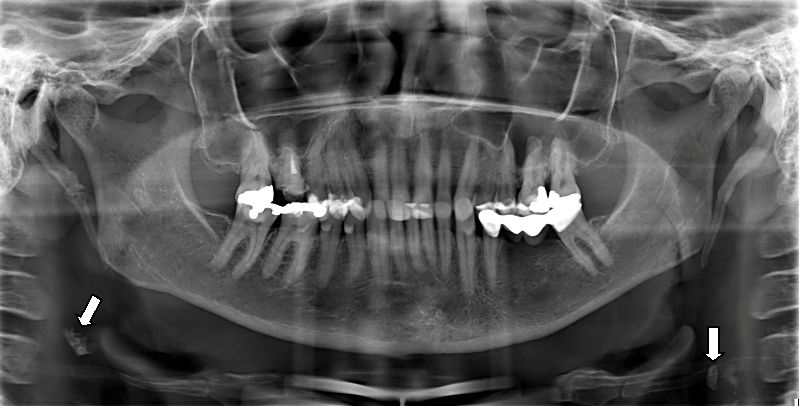

1. What condition can be seen in the following X ray? ( solid arrow)

the calcification within Stensen's duct of parotid